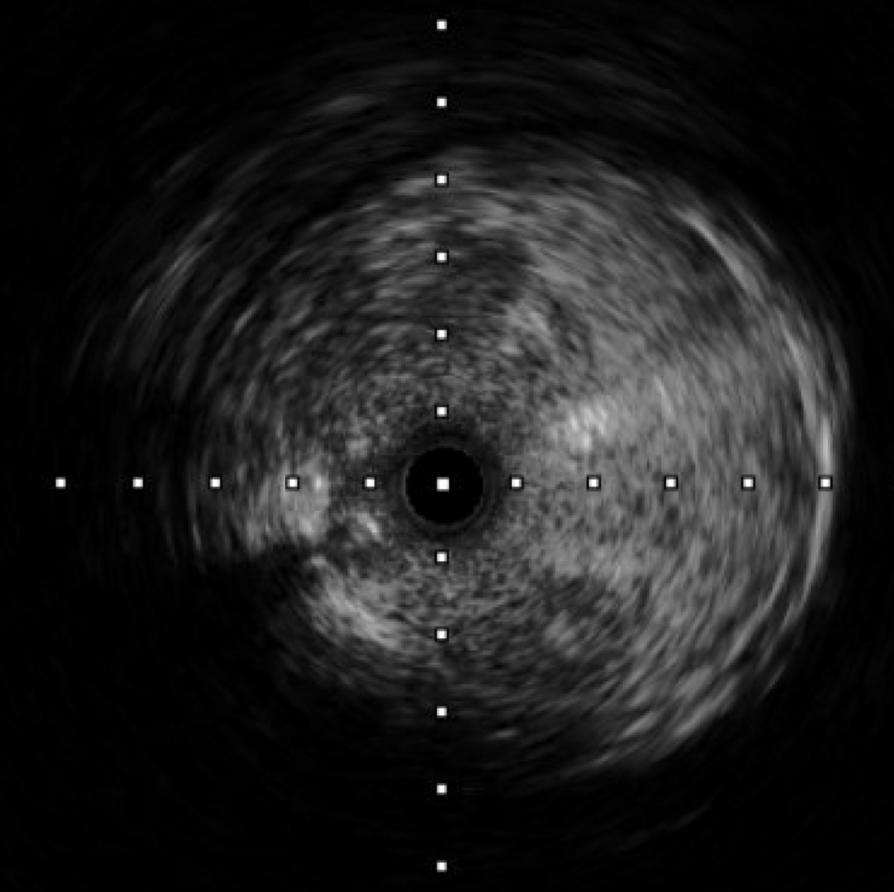

The procedure utilized a hybrid retrograde and antegrade approach. Retrograde access was established via a micropuncture kit under angiography guidance into the distal Superficial Femoral Artery (dSFA), but wiring attempts failed due to an intervening aneurysm, necessitating a switch to the antegrade route from the left brachial artery. A wire escalation technique, assisted by a microcatheter, successfully crossed the extensive CTO, and was met with retrograde microcatheter and externalized via the dSFA puncture site (retrograde access), establishing through-and-through wire access. Following initial balloon predilation and IVUS confirmation of diffuse thrombus, extensive angioplasty was performed. Definitive treatment involved deploying multiple overlapping GORE¢ç VIABAHN¢ç Endoprosthesis diameters (from 6mm to 8mm) from the dSFA proximally to the pEIA via left femoral access, effectively treating the long occlusion and excluding the aneurysm. A COOK Zilver Flex iliac stent reinforced the proximal landing zone. The stented segment was rigorously post-dilated up to 12 atm. The procedure concluded with a Drug-Eluting Balloon (DEB) PTA (BOSTON Ranger Paclitaxel-Coated PTA Balloon Catheter) to the dSFA to mitigate restenosis in the non-stented region. Final angiography confirmed good flow without distal embolization.